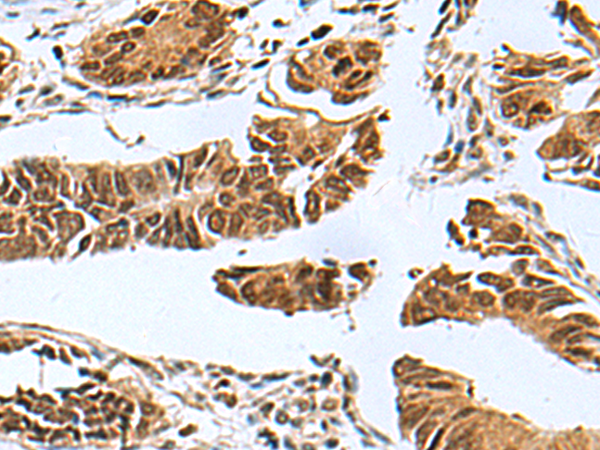

ELISA, IHC |

IHC positive control: |

Human colorectal cancer |

IHC Recommend dilution: |

50-200 |